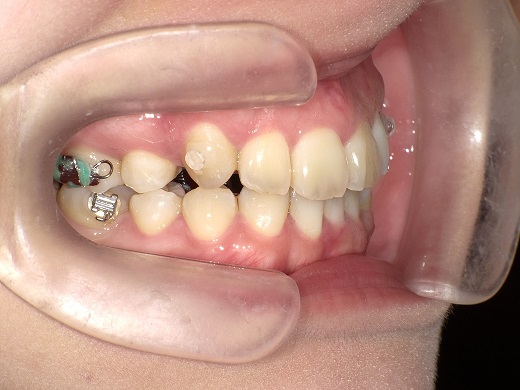

治療前左側

治療中左側